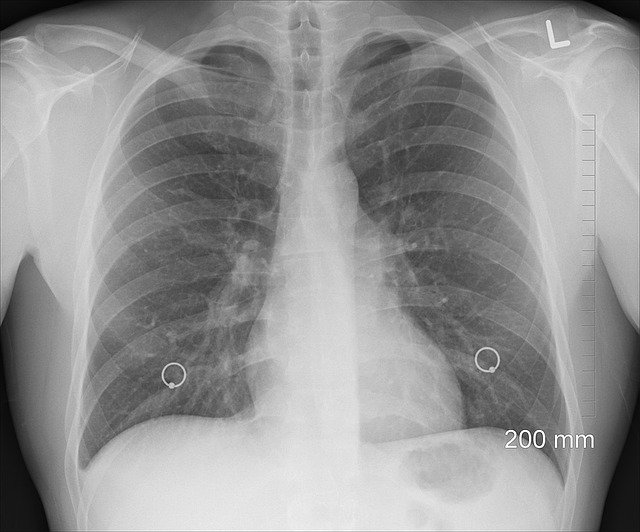

もう一つは、風邪をこじらせ、今度は本格的に良くならないので、通訳さんを連れて診療所に行きました。症状から念の為にレントゲン写真を撮る事になるのですが当時は海沿いの小さな村に住んでいたので、大きな町まで出て胸部のレントゲン写真を撮りに行くことに。

結果は幸いにも

気管支炎や肺炎ではありませんでしたが、

この時の費用を保険で負担してもらえて本当に助かりました。